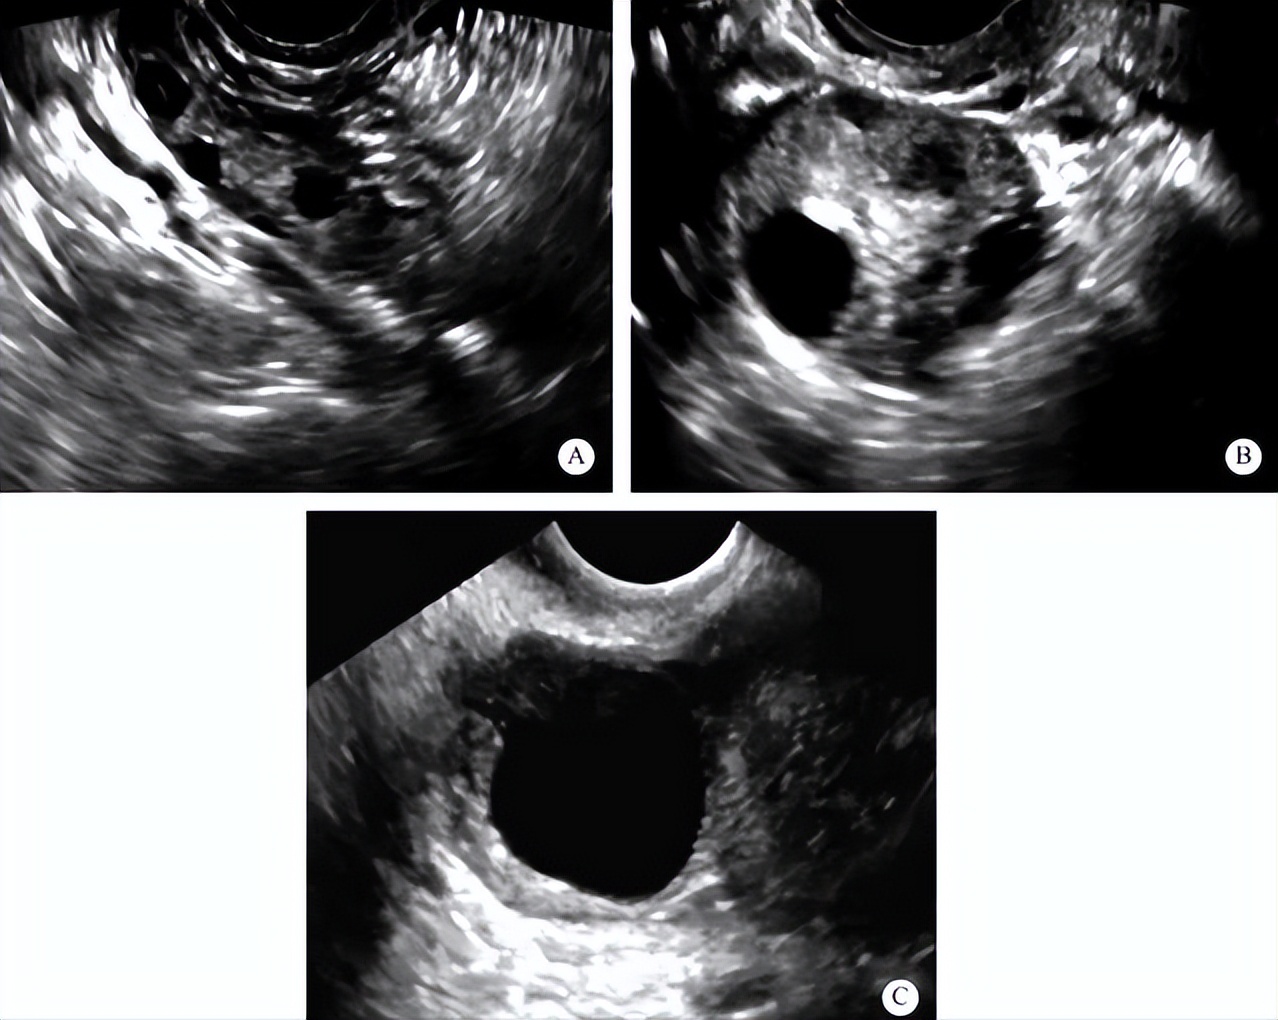

第三步:第2次回诊一般会在月经的第 9-10 天,一样抽血和做超声检查。此时应该会有一个大致排卵的日期。

第四步:第3-4次回诊时应该卵泡已接近排卵期(优势卵泡大小1.8~2.0 cm),此时有两种选择:

1、纯自然周期:持续每日以超声检查和血清激素监测至 “卵泡消失日”(= 取卵日 / Day 0)。所以如果是Day 5 冷冻囊胚,植入日就会在卵泡消失日的五天后。